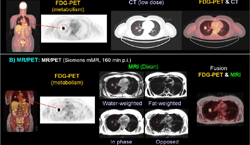

The objective of the study was to gauge the value of combining two molecular imaging agents for cancer imaging with a hybrid molecular imaging system. Researchers used a positron emission tomography (PET)/computed tomography (CT) system, which combines both nuclear medicine and X-ray technology to produce images that provide information about both physiological processes and structural anatomy.

All PET imaging agents are not alike. Medical isotopes are often labeled with an antibody, peptide or any number of other useful molecules that guide the medical isotope directly to its target. One of the most prevalently used imaging agents is 18F-fluorodeoxyglucose (18F FDG), a glucose analog that is metabolized by cells as fuel. This is useful because cancer cells are metabolically hyperactive compared to healthy cells. PET imaging with 18F FDG will show these areas of increased metabolism as “hot spots” on scans. But while it is an excellent agent, it can still miss some cancer lesions, such as those in the skeleton. For this study, researchers compare the results of 18F FDG and sodium fluoride-18 (18F NaF), another PET imaging agent that has been shown to provide superior functional imaging of skeletal tissue, both separately and together.

For this prospective study, investigators recruited 78 patients with proven cancers and scanned them separately using 18F NaF PET/CT and 18F FDG PET/CT imaging methods. Participants then received a third PET/CT scan using 18F NaF and 18F FDG simultaneously. Results of all three imaging studies were then analyzed for their usefulness in evaluating tumor malignancy. Researchers found that combined 18F NaF and 18F FDG PET/CT imaging provided good-quality imaging of both skeletal and extra-skeletal malignant lesions from breast, lung, colorectal and other cancers.